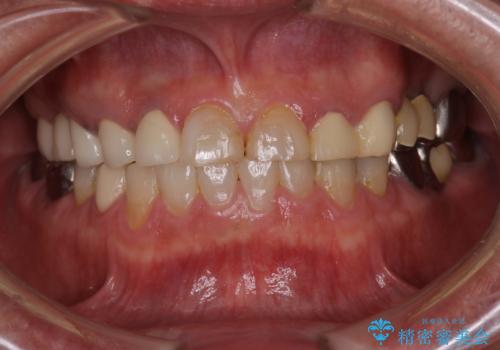

歯肉からの出血 適合の悪い銀歯をオールセラミックのブリッジにやり替え

以前の被せ物を除去し、仮歯に変えてすぐに異和感がとれました。

歯周治療を行い、歯肉が引き締まってから補綴治療しました。